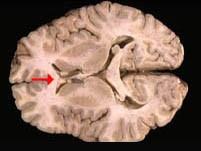

如图箭头所示为大脑哪个部位 ( )A、穹窿B、中脑导水管C、胼胝体D、透明隔E、前连合一、单项选择题

问题 如图箭头所示为大脑哪个部位 ( )

选项 A、穹窿 B、中脑导水管 C、胼胝体 D、透明隔 E、前连合 一、单项选择题

答案 C